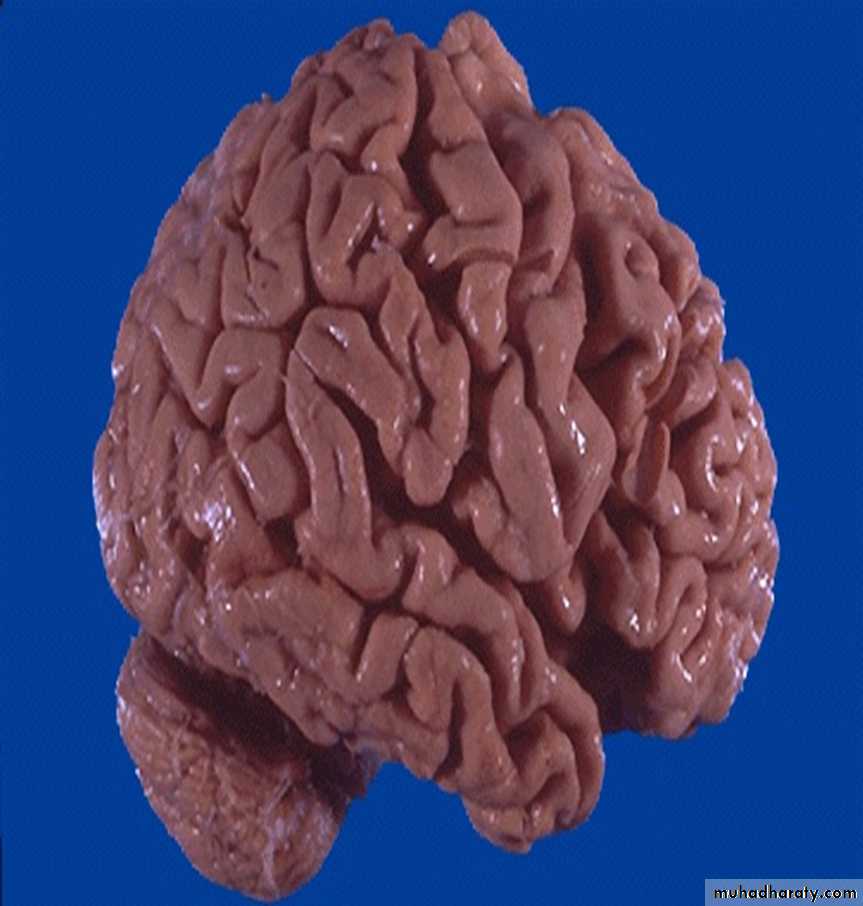

60 years male with "right sided" heart failure. (liver)

Description and diagnosischronic passive congestion of the liver. dark red congested regions that represent accumulation of RBC's in centrilobular regions.